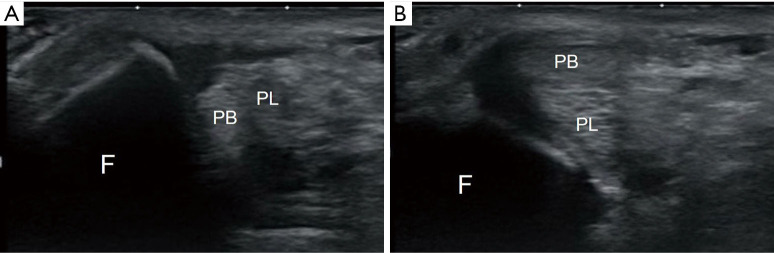

腓肠肌由腓骨长肌(PL)和腓骨短肌(PB)肌腱组成,容易在解剖学上的特定部位或腱鞘内受伤。腓总肌腱脱位(PTD)常被误诊为外侧踝关节扭伤,因为其发生频率低于外侧踝关节扭伤。腓肠肌后沟的解剖变异、软组织过度充盈以及腓肠肌附属肌的存在是导致 PTD 的病因。根据涉及腓骨网膜上缘(SPR)和纤维软骨脊的损伤模式,PTD 被分为四种类型。诊断包括识别触痛点和使用包括核磁共振成像(MRI)和超声波成像在内的成像技术。包括膝下石膏在内的保守治疗成功率不一,有些患者会发展为复发性 PTD(RPTD),这就需要考虑手术治疗。RPTD患者如果能自行再现脱位,诊断就很容易;但在许多病例中,这是不可能的。在这种情况下,鞘内注射后进行超声波检查可有效确认是否存在假性胃袋。如果在超声波检查中发现假性胃袋,就可以诊断为 RPTD。截骨术、软组织手术和沟槽加深技术等手术方法可用于稳定腓肠肌腱。软组织手术,尤其是 SPR 重接术,已成为首选方案,其效果与截骨术相当,但并发症较少。鞘内脱位是一种独特的 PTD 亚型,可通过超声波检查进行诊断。在这种类型的半脱位中,SPR未见损伤,PL和PB肌腱的位置互换。手术治疗可能包括切除滑膜和修复 SPR。对于因 PB 肌腱纵向断裂而并发 PTD 的病例,可对撕裂区域进行缝合,或对剩余的肌腱进行管状切除,以部分切除变性的肌腱。本文旨在介绍 PTD 的诊断和治疗方法。

The peroneus muscles, consisting of the peroneus longus (PL) and peroneus brevis (PB) tendons, are vulnerable to injury at anatomically specific sites or within tendon sheaths. Peroneal tendon dislocation (PTD) is often misdiagnosed as a lateral ankle sprain as it occurs at a lower frequency than a lateral ankle sprain. Anatomical variations in the retromalleolar groove, soft tissue overstuffing, and presence of accessory peroneal muscles contribute to the etiology of PTD. PTD has been classified into four types based on injury patterns involving the superior peroneal retinaculum (SPR) and fibrocartilaginous ridge. Diagnosis involves recognizing tender points and using imaging including magnetic resonance imaging (MRI) and ultrasonography. Conservative treatments, including below-knee plaster casts, have varying success rates, and some patients progress to recurrent PTD (RPTD), prompting consideration of surgical interventions. Diagnosis is easy in patients with RPTD who can reproduce the dislocation by themselves; however, in many cases, this is not possible. In such cases, ultrasonography after intrasheath injection is effective in confirming the presence of a pseudo-pouch. RPTD can be diagnosed if a pseudo-pouch is identified during ultrasonography. Surgical approaches such as osteotomy, soft tissue procedures, and groove deepening techniques are used to stabilize the peroneal tendons. Soft tissue procedures, especially SPR reattachment, have emerged as a preferred option, demonstrating outcomes comparable to those of osteotomy, with fewer complications. Intrasheath subluxation, a unique PTD subtype, is diagnosed using ultrasonography. In this type of subluxation, no damage to the SPR is observed, and the positions of the PL and PB tendons are interchanged. Surgical intervention may involve excision of the synovium and SPR repair. In cases of PTD complicated by a longitudinal rupture of the PB tendon, suturing of the torn area or tubularization of the remaining tendon for partial resection of the degenerated tendon can be performed. The purpose of this article is to describe the methods for diagnoses and management of PTD.